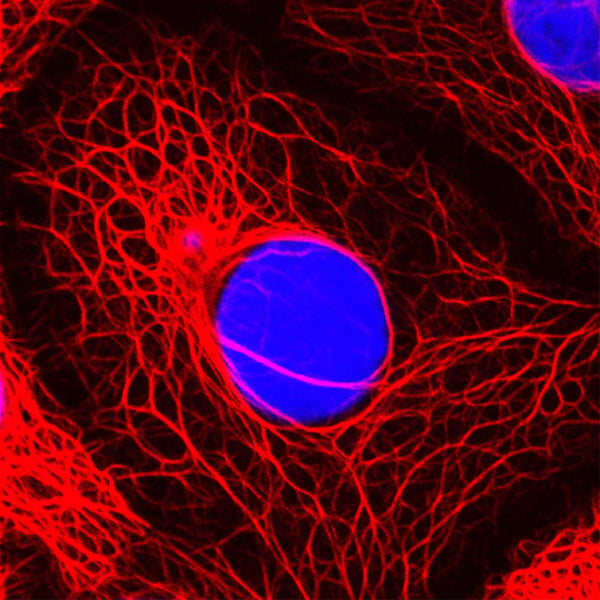

Der Mensch nutzt nur einen Bruchteil seines Gehirns

Zwar keine Ernährungsweisheit, aber ein Gesundheitsmythos ist, dass der Mensch gar nicht die volle Leistung des Gehirns ausschöpfe. Einmal heißt es 10 Prozent, ein andermal 25 Prozent. Mehr unserer Hirnkapazitäten nutzen wir nicht? Doch, tatsächlich nutzt der Mensch alle Bereiche seines Gehirns. Untersuchungen haben gezeigt, dass es keine inaktiven Teile gibt. So verführerisch der Gedanke an noch ungenutzte Areale und Möglichkeiten wie Telepathie und Telekinese sein mag, sie bleiben Fantasterei.

>> Hier finden Sie weitere spannende Mythen rund um unser Gehirn.